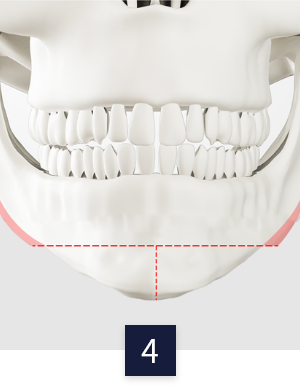

CASE 03

ㅡ절골

수술 방법

수술 전 턱

무턱 or 주걱턱 등 맞는

수술법을 찾아 수술 진행

턱 끝 전진술

턱 끝 뼈를 절골 후

앞으로 움직인 후 고정

턱 끝 후진술

뒤로 움직인 후 고정